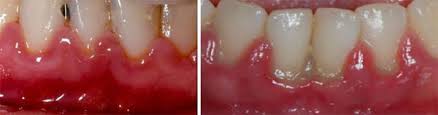

Клинические проявления воспаления десен у детей достаточно выражены. Ребенок начинает жаловаться на зуд в деснах и боль при приеме пищи. При осмотре можно заметить значительную гиперемию и отечность слизистых оболочек. В более тяжелых случаях наблюдается кровоточивость и отек межзубных сосочков. Если в ротовой полости развивается воспаление, красные десны у ребенка – это первый сигнал о серьезных проблемах. Важно обратиться к врачу на этом этапе, чтобы предотвратить переход гингивита в хроническую форму и надеяться на быстрое выздоровление.

Хроническое воспаление десен, возникающее при отсутствии терапии, приводит к развитию хронического процесса, который отличается менее выраженной симптоматикой и отсутствием сильной болезненности. Однако это состояние не менее опасно. Десневая ткань утолщается и разрастается, иногда закрывая часть зуба. Цвет десен становится синюшным, и даже легкое нажатие на них может вызвать обильное кровотечение. Лечение гингивита требует времени и усилий. Поэтому важно не игнорировать болезнь и обращаться к врачу при первых признаках дискомфорта в ротовой полости или даже при незначительных изменениях состояния десен.